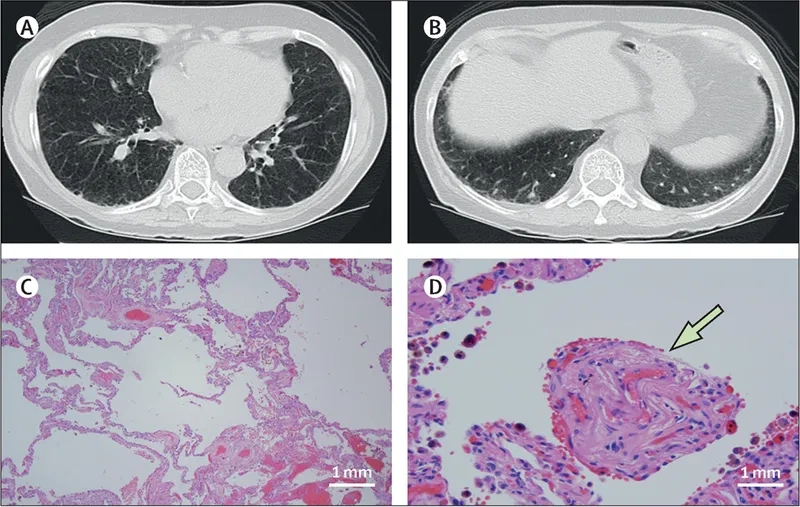

How pulmonary hypertension is diagnosed clinically